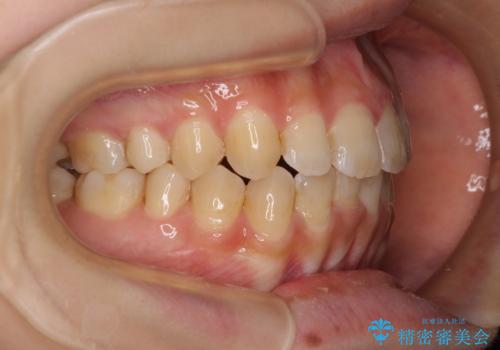

上顎歯列が前方にあり、口元が閉じにくくなっていたため、既に装着されている装置を使用して上顎歯列全体を後方に移動させていくこととしました。

舌の突出癖の影響か、なかなかスペースが閉じきらず、治療期間は予定よりも長期間となりました。

舌突出癖改善のトレーニングの重要性を認識することとなりました。